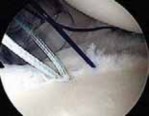

Anchor Placement and Capsulolabral Plication

With the glenoid prepared and the tissue mobilized, fixation begins at the most inferior aspect of the lesion, typically at the 5:30 or 6 o'clock position. Modern fixation relies on either biocomposite or all-suture anchors, typically 1.5 mm to 2.9 mm in diameter. The drill guide is introduced through the anteroinferior portal, and the anchor is deployed on the articular margin (1-2 mm onto the articular cartilage face) to recreate the anatomical labral bumper. The trajectory of the drill is paramount; it must be directed slightly medially to avoid penetrating the articular surface of the glenoid vault.